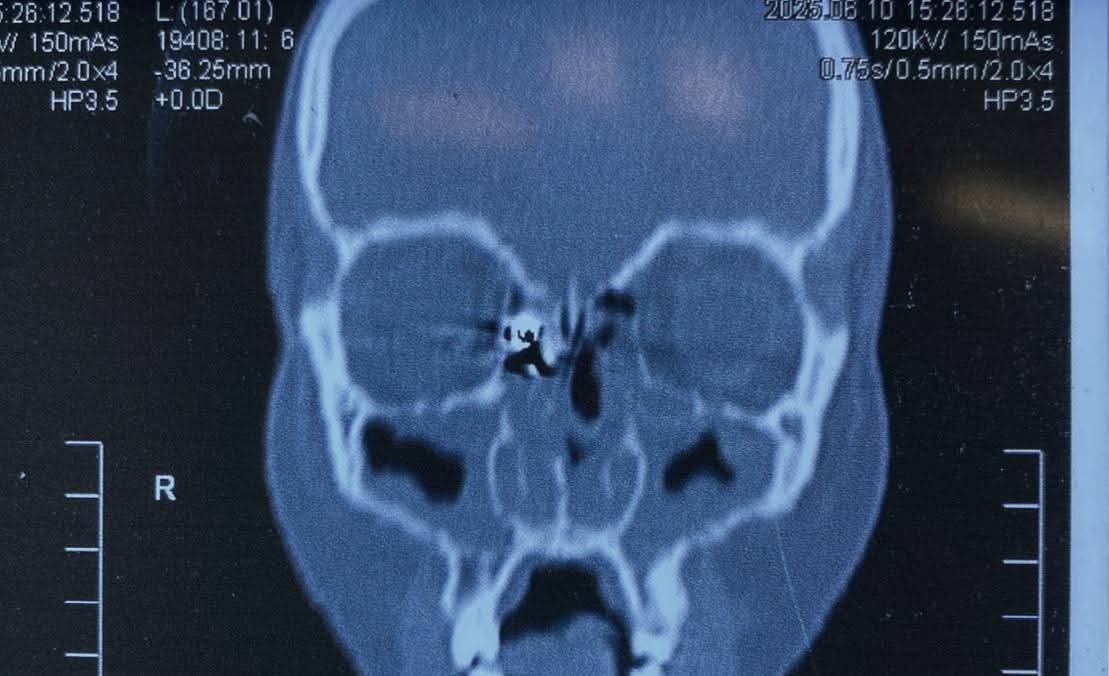

وكانت المريضة قد حضرت إلى المستشفى تعاني من نزيف بالأنف وتورم بالعين، عقب ادعائها الإصابة بطلق ناري من بندقية صيد، وعلى الفور، تم إجراء أشعة مقطعية على الأنف والجيوب الأنفية، والتي أظهرت وجود جسم غريب معدني مستقر داخل الجيوب الأنفية الغربالية.

وعلى إثر ذلك، تم التعامل مع الحالة بشكل عاجل، حيث جرى إدخالها إلى عمليات قسم الأنف والأذن والحنجرة، وتمكن الدكتور علاء عبدالسميع، أستاذ مساعد الأنف والأذن والحنجرة، بمشاركة الفريق الطبي المعاون من أطباء وتمريض العمليات، من استخراج الطلقة بنجاح باستخدام منظار الجيوب الأنفية، دون حدوث أي مضاعفات.